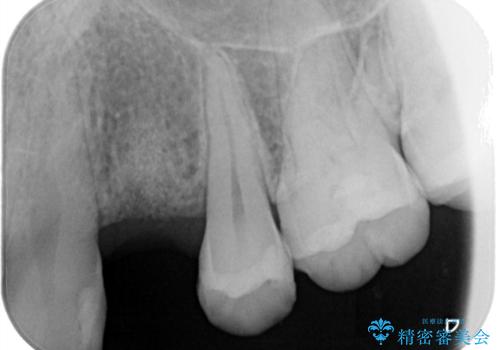

虫歯がかなり進行していて根っこしか残っていない状態でした。日々の歯ブラシが上手く出来ていなくプラーク(細菌の塊)も溜まっている状態でした。

歯を保存するのは出来ないと診断し抜歯した後にインプラントで治療を行いました。